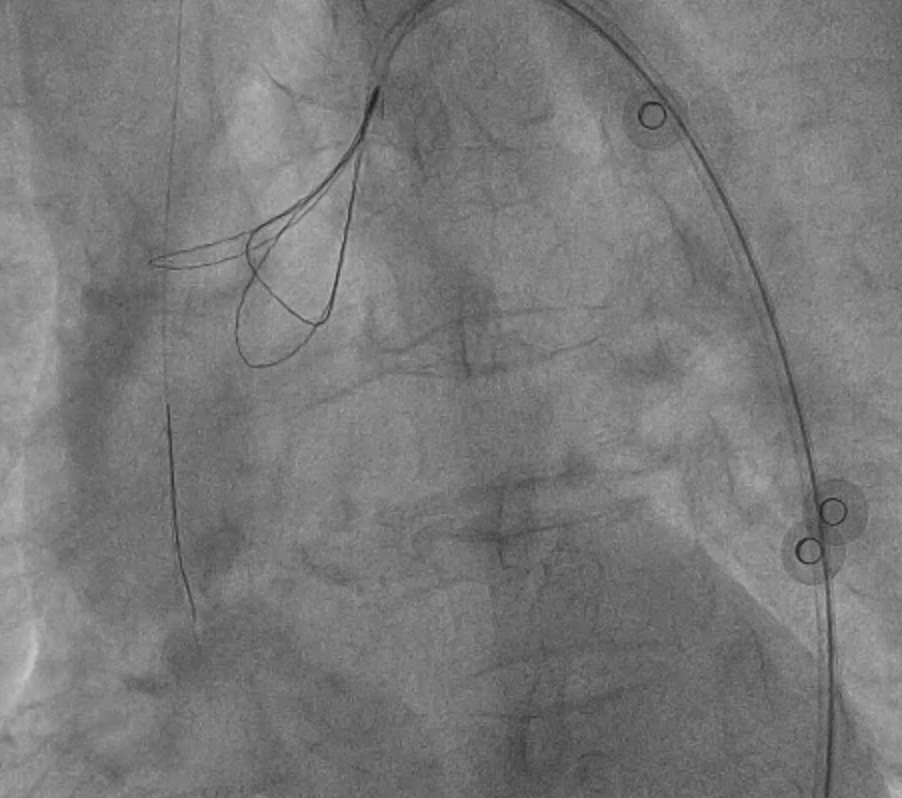

Further predilatation was performed with an NC 3.0, but this was complicated by no-relow. The patient's hemodynamics deteriorated, with bradycardia and hypotension. We administered different medications, followed by temporary pacing lead insertion and penumbra for thrombus aspiration.

Given the unstable hemodynamics, we retracted the system to the brachial artery and established a new setup via the right femoral. Instead of a long stent, we implanted two shorter stents, with the assistance of a guide extension. After successful deployment, we peformed post-dilation.

Then we proceeded to retrieval of the dislodged stent. We pushed the old system back to the aorta and we snared the wire with ENsnare. The proximal portion of the stent was significantly deformed and could not go into the JR4 guiding catheter from femoral side. We tried different methods including using a larger and longer sheath, manipulations to optimise alignment, changing to a different snare but we still failed. At last, we successfully retrieved the stent with the use of biopsy forceps.

Then we proceeded to retrieval of the dislodged stent. We pushed the old system back to the aorta and we snared the wire with ENsnare. The proximal portion of the stent was significantly deformed and could not go into the JR4 guiding catheter from femoral side. We tried different methods including using a larger and longer sheath, manipulations to optimise alignment, changing to a different snare but we still failed. At last, we successfully retrieved the stent with the use of biopsy forceps.